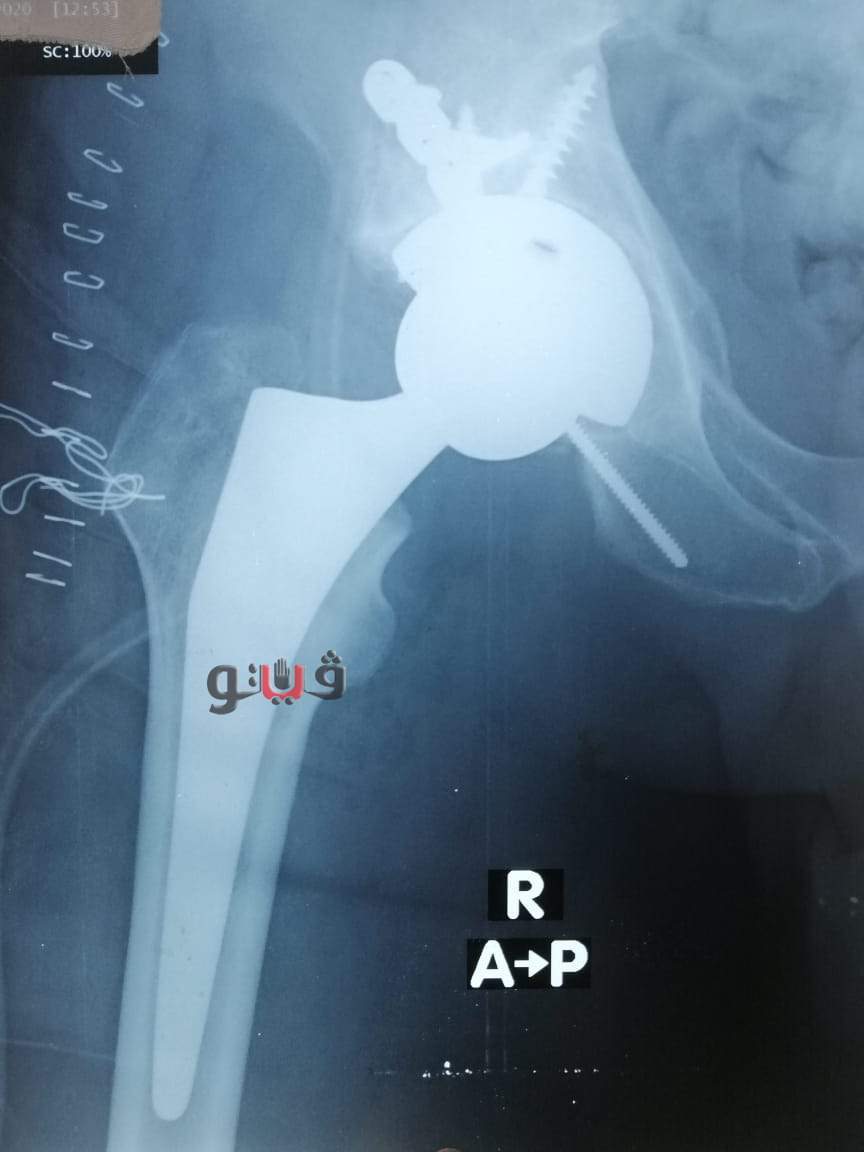

وكان المريض ضمن الحالات الحرجة لقوائم الإنتظار حيث تمكن الفريق الطبى من اجراء استبدال مفصل فخذ صناعي كامل حيث استغرقت العمليه حوالي ثلاث ساعات وتعد هذه العملية من الجراحات المتقدمة ذات المهارة الخاصة.

كما اطمأن وكيل الصحة على صحة المريض حيث عاد الي حالته الطبيعيه وبحالة مستقرة.